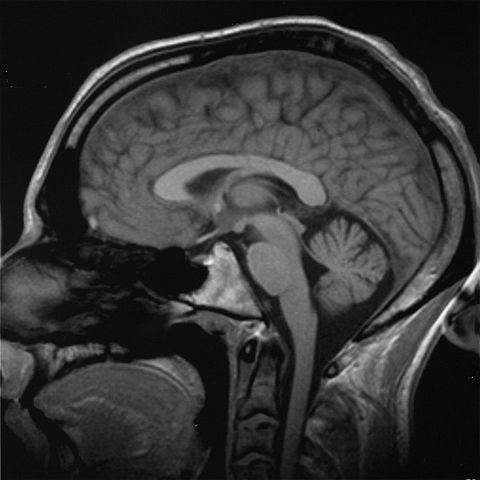

- Description: saggital transection through the human brain

- Source: this is my very own brain. MRI, 10/13/2000

- Author: Christian R. Linder